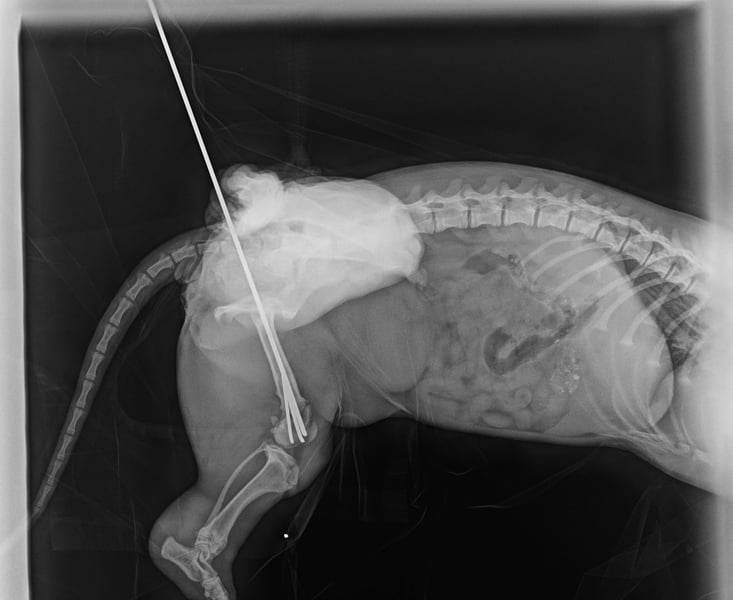

Ilse hatte einmal eine Besitzerin, doch ihr Leben war nicht leicht. Als sie aus dem Hof entkam, wurde sie von einem Auto angefahren und brach sich ein Bein. Zum Glück konnte sie operiert werden – die OP war erfolgreich, und Ilse läuft und rennt wieder ganz normal! Die Metallstifte werden in Kürze entfernt.